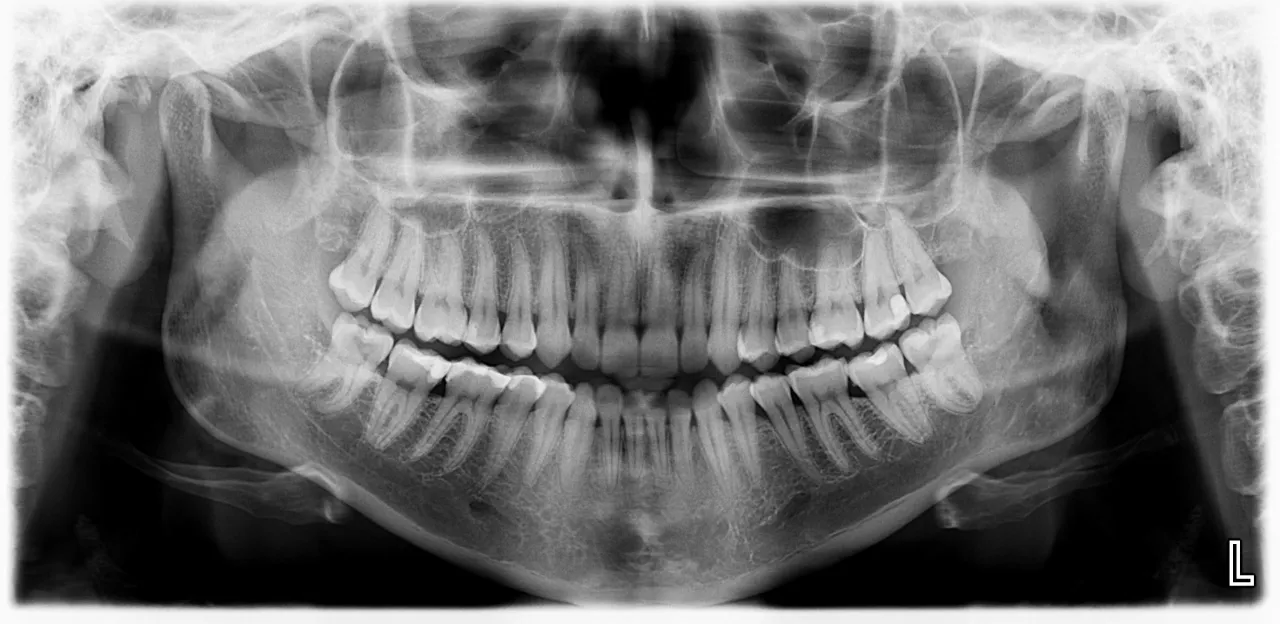

Nawet najbardziej dokładne badanie kliniczne ma swoje ograniczenia. Wiele problemów zdrowotnych jamy ustnej kryje się pod powierzchnią dziąseł i wewnątrz kości, niewidocznych gołym okiem. Dlatego właśnie zdjęcia rentgenowskie, zarówno pantomograficzne (przeglądowe), jak i punktowe, są absolutnie kluczowe w mojej diagnostyce. Pozwalają mi ocenić stan korzeni zębów, sprawdzić, czy nie ma tam stanów zapalnych, torbieli czy zmian okołowierzchołkowych. Widzę również poziom kości wokół zębów, co jest niezwykle ważne w diagnostyce chorób przyzębia. Zdjęcia RTG ujawniają także ukryte ubytki próchnicowe, które rozwijają się między zębami i są niewidoczne podczas standardowego przeglądu.

Zęby zatrzymane, torbiele, stany zapalne: Ukryte zagrożenia pod kontrolą

Dzięki zdjęciom rentgenowskim jestem w stanie zdiagnozować szereg patologii, które bez nich pozostałyby niezauważone, stanowiąc potencjalne zagrożenie dla zdrowia pacjenta:

- Zęby zatrzymane: Często są to ósemki, które nie wyrznęły się prawidłowo i mogą powodować ból, stany zapalne lub uszkadzać sąsiednie zęby.

- Torbiele: Patologiczne jamy wypełnione płynem, które mogą rozwijać się w kości szczęki lub żuchwy, często bezobjawowo, a ich wzrost może prowadzić do zniszczenia kości.

- Stany zapalne wokół wierzchołków korzeni: Niewidoczne klinicznie, ale doskonale widoczne na RTG jako przejaśnienia w kości, świadczące o przewlekłym procesie zapalnym, który wymaga leczenia kanałowego lub usunięcia zęba.

- Resztkowe korzenie: Fragmenty korzeni zębów, które pozostały w kości po wcześniejszych ekstrakcjach i mogą być źródłem infekcji.

- Zmiany w stawach skroniowo-żuchwowych: Zdjęcie pantomograficzne pozwala również na wstępną ocenę tych stawów, co jest pomocne w diagnostyce problemów ze zgryzem czy bruksizmem.